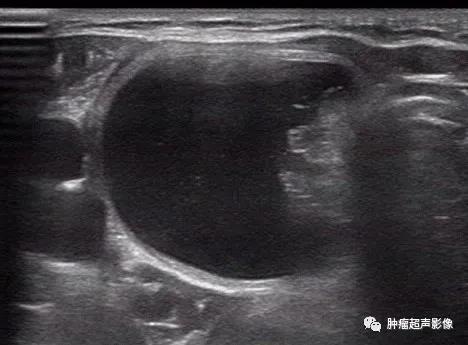

3、内部实性结构:包括偏心单发壁结节、实性部分形态不规则、实性部分向周边的壁伸出多个较细的分隔(“蜘蛛征”),此征象诊断的敏感性及特异性一般。

多年体检诊断为结节囊性变,肿块整体形态不规则,内部实性部分形态也不规则,因此我考虑乳头状癌,术后病理证实为乳头状癌

来自微信会诊病例:形态不规则,微钙化,实性部分向周边的壁伸出多个较细的分隔(“蜘蛛征”),血流由中心向四周发出的分支动脉血流(“烟花征”)符合典型囊性乳头状癌,术后病理证实为乳头状癌